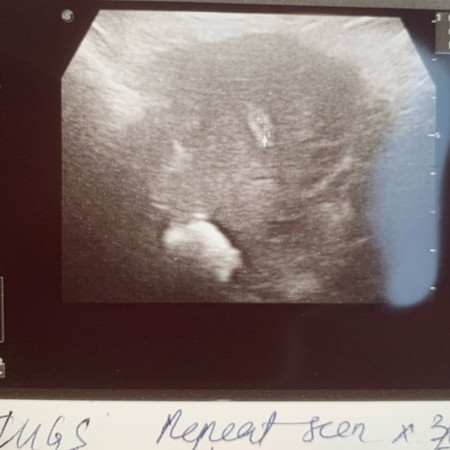

Scan pregnancy confirmation

Saya check upt samar samar. Pergi scan kantung dah ada tapi kecil lagi. Dinding rahim pun menebal. Tapi bila check pakai clearblue result dia not pregnant. Saya rasa down 😢